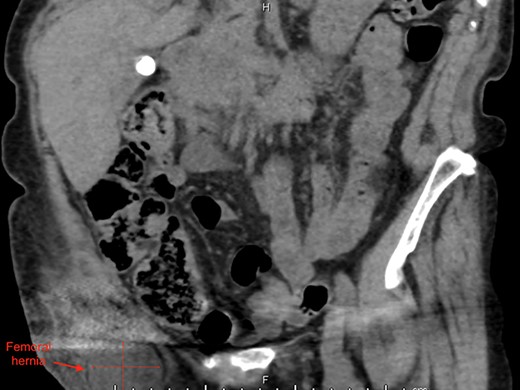

An 87-year-old Caucasian female presented to the emergency department with a 5-day history of worsening right groin pain, with an associated 2-day history of generalized malaise and fatigue. She denied fever, nausea and vomiting or signs of bowel obstruction. Her past medical history included previous right total hip replacement, type 2 diabetes mellitus and chronic renal impairment. Her vitals were normal, and examination revealed a tender right groin lump below the level of the pubic tubercle approximately 4 × 4 cm in size, with overlying erythematous skin changes. Biochemical investigation revealed a normal white cell count of 10.0 × 109/L and neutrophil profile of 7.8 × 109/L but an elevated C-reactive protein (CRP) of 190 mg/L. Contrast-enhanced computed tomography (CT) scan revealed a hypodense rounded lesion measuring 3.8 × 4.3 × 3.1 cm, medial to the right femoral vessels and extending lateral to and below the level of the pubic tubercle in the proximal anterior thigh, most consistent with a incarcerated femoral hernia (Figs. 1–3). The presence of right total hip replacement artifacts precluded accurate assessment for communication of the lesion with the peritoneal cavity.

Axial view of right femoral hernia, note the significant image distortion from the right total hip replacement beam artifacts.